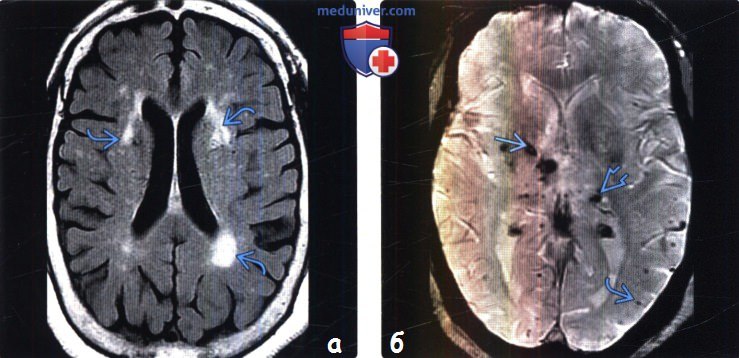

Есть очаги в головном мозге

Есть очаги в головном мозге 114 фото